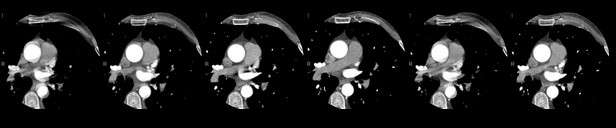

CTA's were taken on 2-2017 and 11- 2019 app. 34 months apart on the same Toshiba Aquillion

Total calculated Agatston score (excluding stent) is: 414 ( prior 382) LAD: 209 (prior 210) LCX: 197 (prior 171) RCA: 8 (prior 1)

2020 photo courtesy of Dr Shaw, showing stent in LAD and disease in LCX

end view of an artery seen on right side. Below 2020

2020 curved multi planar images showing stent in LAD(left) and disease in LCX tks Dr. Shaw for great images, end view of arteries are seen on right. |